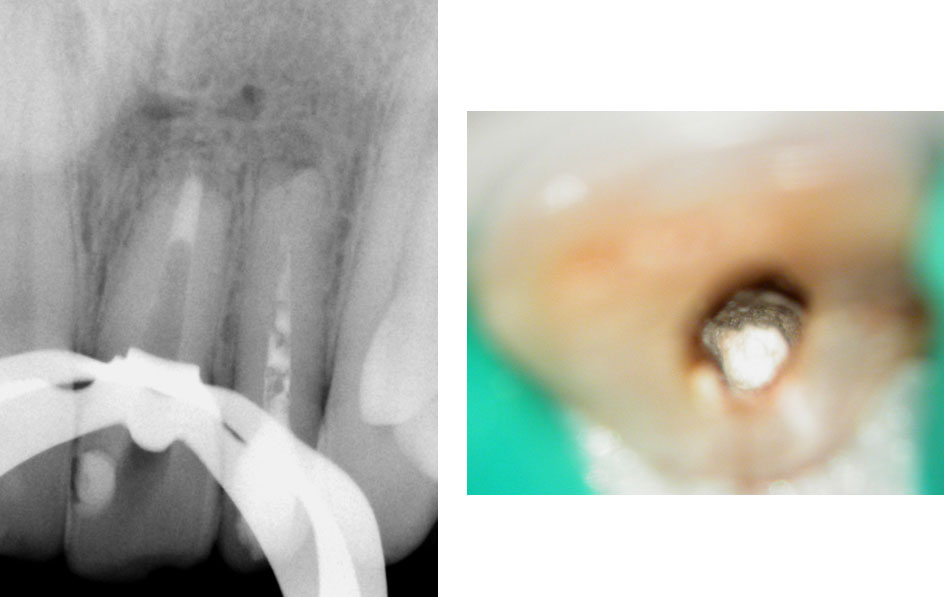

Red arrow shows calcification covering the MB2. Removal of this calcification with ultrasonics reveals the missed MB2(yellow arrow)

5 canals cleaned, shaped and obturated after 10 days of calcium hydroxide. MB1 and MB2 had seperate portals of exit. DB2 merged intoDB1. Palatal two portals of exit.